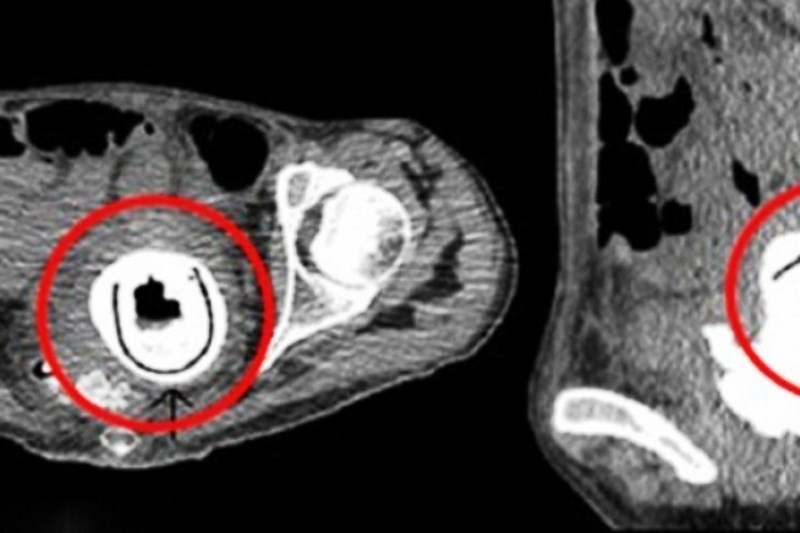

Γιατροί σε νοσοκομείο της Βρετανίας έμειναν έκπληκτοι όταν ανακάλυψαν ένα sex toy στον κόλπο μίας 38χρονης γυναίκας, το οποίο, μάλιστα, παρέμενε εκεί για 10 ολόκληρα χρόνια.

Το ερωτικό παιχνίδι, μήκους 12 εκατοστών αποκαλύφθηκε, όταν η γυναίκα υποβλήθηκε σε μια σειρά από ακτινογραφίες, μετά την εισαγωγή της στο νοσοκομείο με συμπτώματα υπνηλίας, κόπωσης, απώλειας βάρους και συχνών ουρολοιμώξεων.